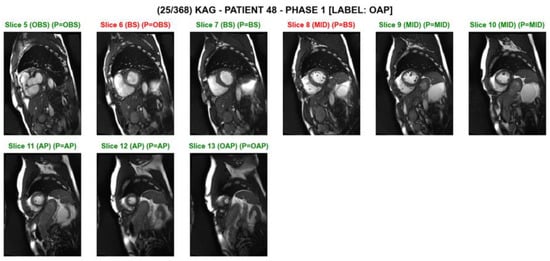

Figure 3. A screenshot of slice level predictions on a series of short axis slices on an individual test subject. The prediction was made by the ‘MobileNet_2layerLSTM’ model. The slice index, the ground truth, and the predicted category are shown above each image. The green text indicates correct classification, while the red text indicates incorrect classification. For example, ‘(BS) (P = OBS)’ indicates that the ground truth is ‘basal’, and the model’s prediction is ‘out-of-basal’.

Table 5 compares prediction results on testing data in a variety of CNN and CNN-RNN models. For a given baseline network, all four CNN-RNN models outperformed the CNN model in all the categories. Among the four baseline models considered, MobileNet produced the highest F1-scores in four out of the five classes. NASNetMobile was relatively poor in predictions. The MobileNet 2-LSTM model resulted in the highest scores in four out of the seven evaluation metrics. The MobileNet Bi-LSTM model resulted in the highest scores in two out of the seven evaluation metrics. Our Python implementation was effective in labeling each slice image as well as in checking the prediction results along with ground truth, as shown in Figure 3. In particular, the model comparisons were possible at an individual subject level. Bidirectional recursive temporal encoders generally outperformed their two-layer unidirectional counterparts, despite parity in model capacity. This indicates that the task of cardiac slice classification can benefit from bidirectional temporal modeling. The performance gap is highlighted in the oap category, e.g., the difference in F1-score between 2-GRU and bi-GRU for NASNetMobile is highest in oap, with a delta of 0.068 F1-score. This can be attributed to the absence of sequential signal from the unidirectional encoder, as there are no image slices that precede the oap category. This further supports the need for sequential modeling in the cardiac cine short axis classification task.